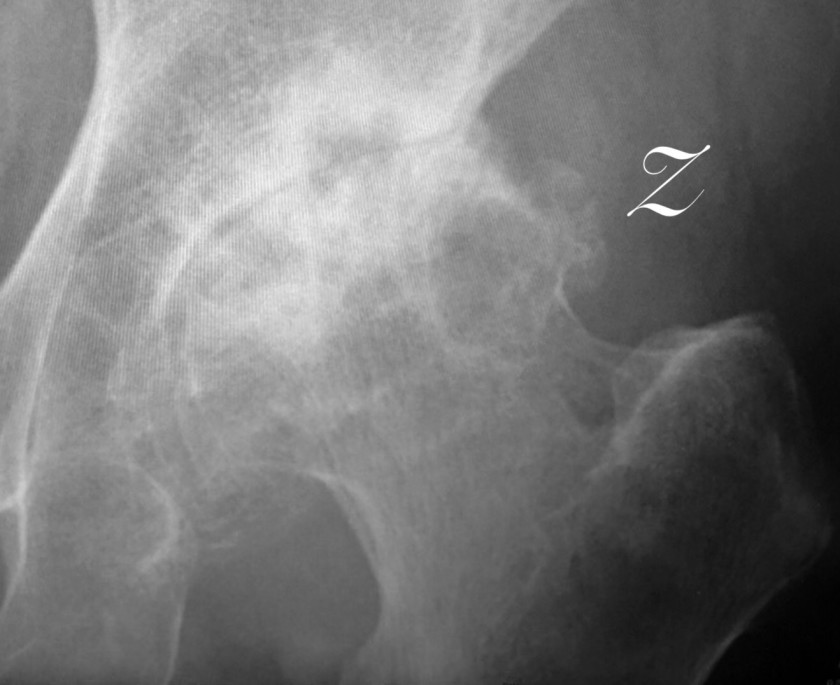

2018/09/24 痛くない方から手術しましょう?

80歳代の女性主訴は⭐️左大腿部痛・歩行障害 某病院整形外科受診 ⭐️右股関節からオペしましょうと言われて以降受診せず先日、友人に紹介され当院受診。診断は両

変形性股関節症 内科系の先生方にはナゼこうなったか❓基礎になった股関節の異常が見つけ出せますか❓さて前医はナゼ患者さんが痛がっている左側ではなく右側の股関節からオペと言われたのか❓ミタメはド派手な右側を一般の方を含めほぼ皆様がオペしたらと言うでしょう。入室時の歩容を見たら容易に理解できますが重症なのは明らかに左側でした。レントゲンでも容易にわかります。よく観察すること。この点は基礎も臨床も同じ。